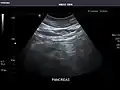

Spleen: Normal in size.

Spleen -